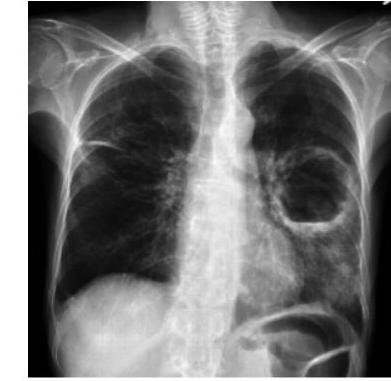

# ABSCESO PULMONAR ## DEFINICIÓN Un absceso pulmonar es la infección e inflamación que resulta en necrosis y cavitación pulmonar caracterizada por el acúmulo de pus. ## CLASIFICACIÓN | PRIMARIOS | Broncoaspiración | | :-- | :-- | | SECUNDARIOS | Cuerpo extraño, tumor, infección sistémica | ## TEMPORALIDAD | AGUDOS | Menos de 6 semanas | | :-- | :-- | | CRÓNICOS | Más de 6 semanas | ## ETIOLOGÍA **ANAEROBIOS DE LA FLORA DE CAVIDAD ORAL** (Peptostreptococcus, Prevotella, Bacteroides y Fusobacterium) Otros agentes: - S. aureus - E. coli - Pseudomonas - Klebsiella - Legionella - Mycobacterium tuberculosis ## LOCALIZACIÓN: - **SEGMENTOS INFERIORES** (parte posterior de los lóbulos superiores y parte superior de los lóbulos inferiores) - Debido a la predisposición de los materiales aspirados - Son más frecuentes en el pulmón derecho. ## EPIDEMIOLOGÍA ## FACTORES DE RIESGO - Compromiso mental - Mala higiene bucal - Alcoholismo - Toxicomanías - Convulsiones - Ventilación mecánica # CLÍNICA - Fiebre - Diaforesis - Tos productiva fétida - Puede haber hemoptisis - Puede haber dolor abdominal o torácico. ## COMPLICACIONES - Empiema - Fístula Broncopleural - Hemoptisis Masiva - Absceso Cerebral Metastásico ## DIAGNÓSTICO ## CLÍNICO - Inicia con la sospecha y los antecedentes del paciente ## ESTUDIO DE IMAGEN La presencia de un absceso se confirma con una imagen torácica que lo evidencie. - **RADIOGRAFÍA DE TÓRAX**: se detecta una cavidad de pared gruesa con un nivel hidroaéreo. - **TAC**: proporciona mejor definición y evidencia más precoz de la cavitación  ## CULTIVO DE ESPUTO Se puede complementar para definir la etiología ## TRATAMIENTO ## 1ra elección: **CLINDAMICINA O AMOXICALV** - Por lo regular el tratamiento se continúa hasta la desaparición del absceso o la presencia de una cicatriz pequeña en el estudio de imagen. ## CASOS GRAVES - Se agrega al esquema **CEFALOSPORINA 30 G, PIPE/TAZO O IMIPENEM** ## QUIRÚRGICO - Indicado en casos complicados, con mala evolución o de **ABSCESO MAYOR A 6 cm**.